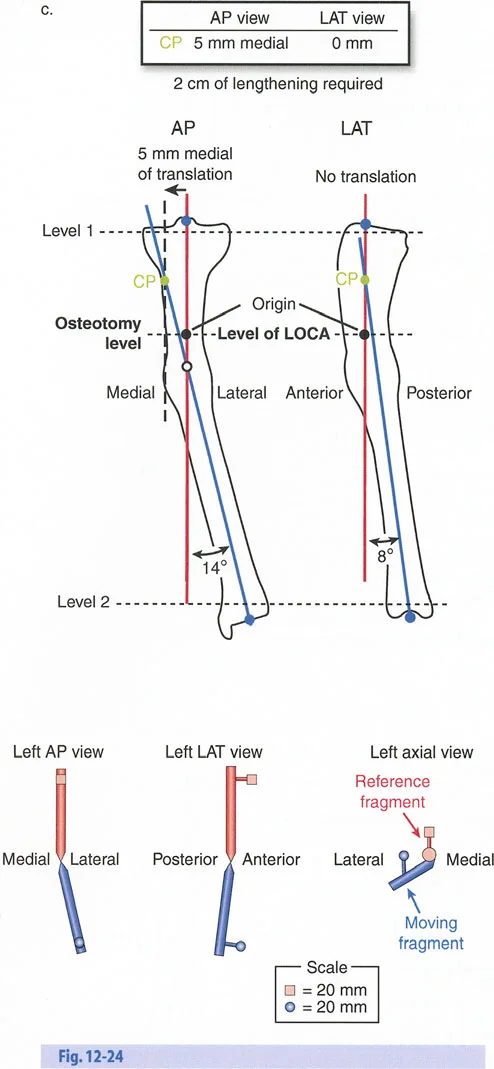

- الأشعة السينية الطويلة للطرفين (Long-leg Standing X-rays): هذه الأشعة ضرورية لتقييم المحور الميكانيكي للطرف بالكامل أثناء الوقوف. تسمح بتحديد مركز دوران الانحراف (CORA) بدقة، وهو النقطة التي يجب أن تتمحور حولها عملية التصحيح.

القياسات الهندسية:

- باستخدام صور الأشعة السينية الطويلة، يقوم الأستاذ الدكتور محمد هطيف بإجراء قياسات هندسية دقيقة لتحديد الزوايا غير الطبيعية (مثل mLDFA و MPTA)، ومقدار القصر، ودرجة الدوران، وأي انحرافات في المحور الميكانيكي. هذه القياسات هي الأساس لتخطيط الجراحة بدقة متناهية.

- قاعدة قطع العظم 1: عندما يمر قطع العظم ومحور تصحيح الانحراف (ACA) كلاهما عبر مركز دوران الانحراف (CORA)، فإن نهايات العظم ستنحرف دون ترجمة (انزياح). يتم استعادة المحور الميكانيكي، وتظل نهايات العظم متقاربة تمامًا، مما يخلق تصحيحًا كلاسيكيًا "إسفينيًا مفتوحًا" أو "إسفينيًا مغلقًا".

- قاعدة قطع العظم 2: عندما يمر محور تصحيح الانحراف (ACA) عبر مركز دوران الانحراف (CORA)، ولكن يتم إجراء قطع العظم على مستوى مختلف (غالبًا بسبب ضعف جودة العظم عند CORA أو مشاكل في الجلد)، فإن نهايات العظم ستنحرف وتخضع لترجمة محسوبة ومقصودة لإعادة محاذاة المحور الميكانيكي.

- قاعدة قطع العظم 3: (للاكمال) عندما يمر قطع العظم عبر مركز دوران الانحراف (CORA)، ولكن يتم وضع محور تصحيح الانحراف (ACA) خارج CORA، سيتم إنشاء تشوه ترجمة جديد، وهو خطأ شائع في وضع المفصلات غير المخطط له جيدًا.

في المنشآت القريبة من المفصل، غالبًا ما نعتمد على قاعدة قطع العظم 2. نظرًا لأنه لا يمكننا قطع العظم بأمان عند خط المفصل تمامًا (مركز دوران الانحراف CORA)، فإننا نقطع العظم في مستوى أدنى في منطقة الميتافيسيس. بعد تحقيق التصحيح الزاوي عبر المفصلات (محور تصحيح الانحراف ACA)، يتم إعادة محاذاة خطوط المحور الميكانيكي بشكل مثالي، ولكن نهايات العظم في موقع قطع العظم تتحرك بالنسبة لبعضها البعض.